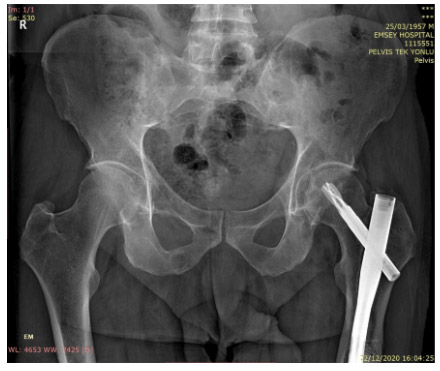

Before the surgery: X-rayhThere are lytic lesions in both acetabulum and the left pelvis (The patient previously had a nail implanted due to a fracture).